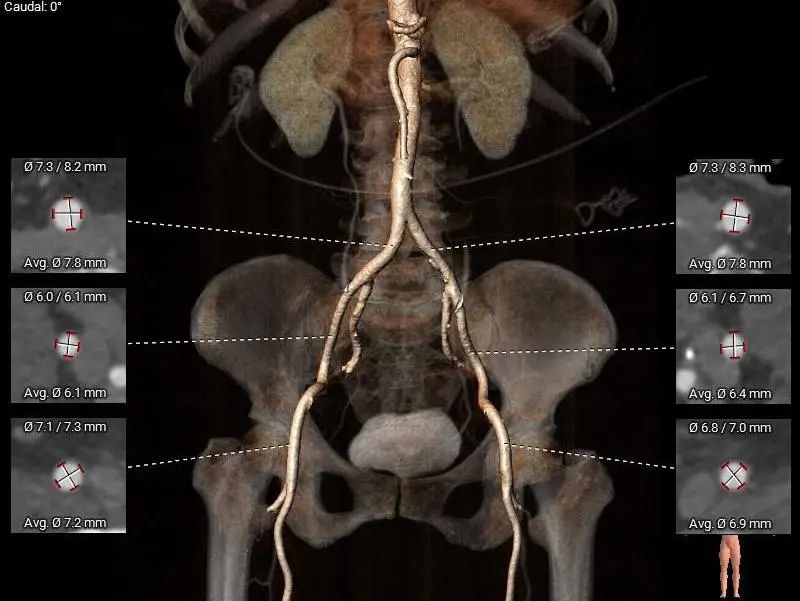

外周入路:

右侧股动脉为主入路,左侧股动脉为辅入路。